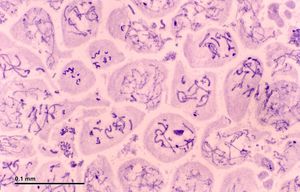

الخلية النطفية Spermatocytes are a type of male gametocyte in animals. They derive from immature germ cells called spermatogonia. They are found in the testis, in a structure known as the seminiferous tubules.[1] There are two types of spermatocytes, primary and secondary spermatocytes (Figure 1). Primary and secondary spermatocytes are formed through the process of spermatocytogenesis (Figure 3).[2]

Primary spermatocytes are diploid (2N) cells. After Meiosis I, two secondary spermatocytes are formed. Secondary spermatocytes are haploid (N) cells that contain half the number of chromosomes.[1]

At puberty, spermatogonia located along the walls of the seminiferous tubules within the testis will be initiated and start to divide mitotically, forming two types of A cells that contain an oval shaped nucleus with a nucleolus attached to the nuclear envelope; one is dark (Ad) and the other is pale (Ap), which can be seen in Figure 3. The Ad cells are spermatogonia that will stay in the basal compartment (outer region of the tubule); these cells are reserve spermatogonial stem cells that do not usually undergo mitosis. Type Ap are actively-dividing spermatogonial stem cells which begin differentiation to type B spermatogonia, which have round nuclei and heterochromatin attached to the nuclear envelope and the center of nucleolus.[4] Type B cells will move on to the adluminal compartment (towards the inner region of tubule) and become primary spermatocytes; this process takes about 16 days to complete.[2][5]

The primary spermatocytes within the adluminal compartment will continue on to Meiosis I and divide into two daughters cells, known as secondary spermatocytes, a process which takes 24 days to complete. Each secondary spermatocyte will form two spermatids after Meiosis II.[1]

Histological section through testicular parenchyma of a boar. 1 Lumen of Tubulus seminiferus contortus, 2 spermatids, 3 spermatocytes, 4 spermatogonia, 5 Sertoli cell, 6 Myofibroblasts, 7 Leydig cells, 8 capillaries